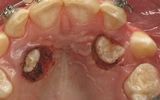

- Gengivectomia-gengivoplastica

- Allungamento di corona

- Mucositi-perimplantiti